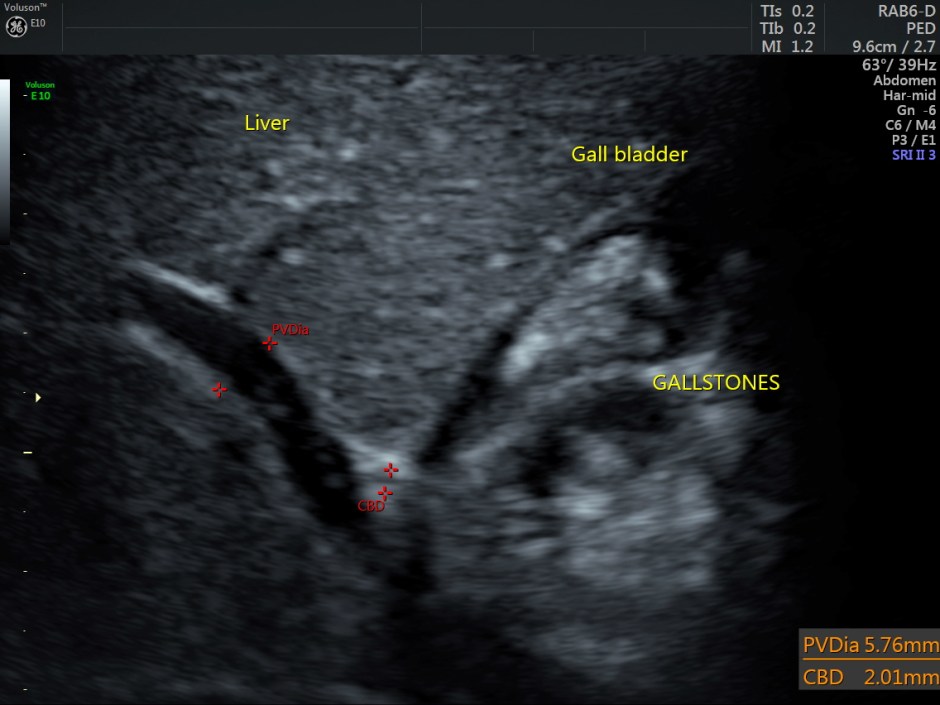

The scan revealed the following findings:

Cholelithiasis

Normal appearing liver and portal venous system.

Other laboratory studies may be directed by history, physical examination, peripheral smear, and other laboratory findings. Ultrasonography is used to estimate the spleen size since the physical examination occasionally does not detect significant splenomegaly. Chest radiography, electrocardiography (ECG), and other studies are used to evaluate cardiopulmonary status.